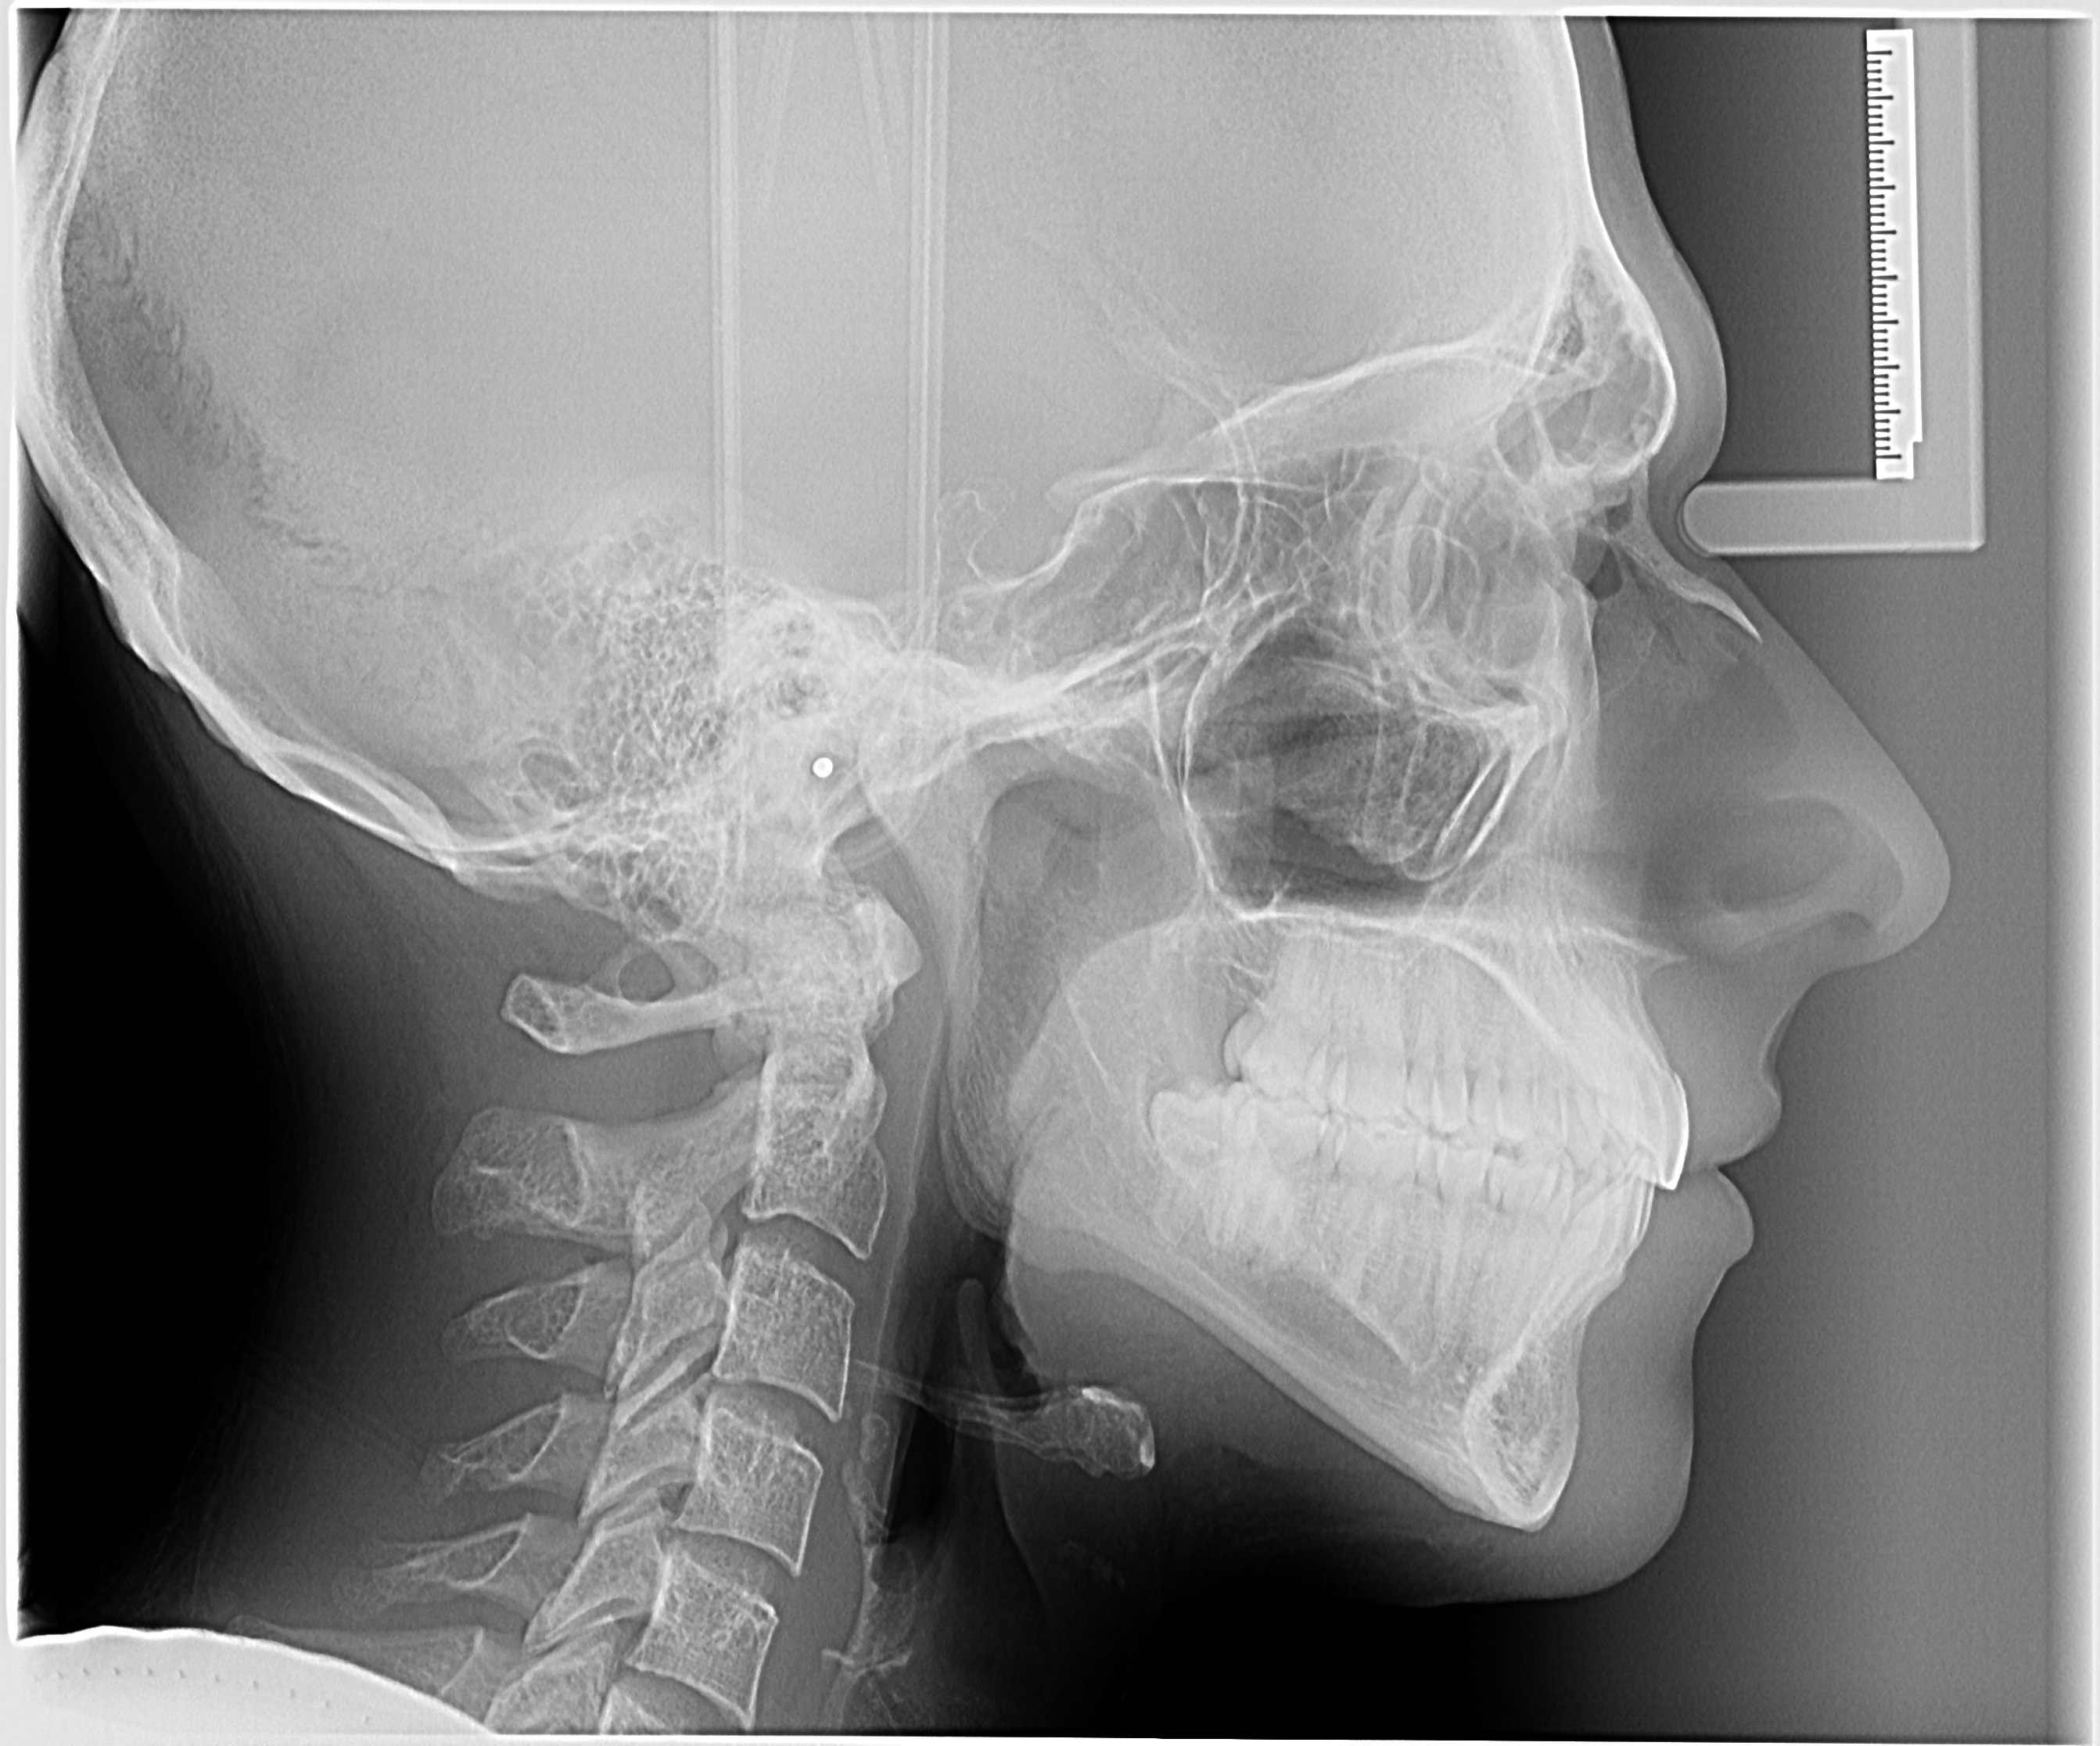

Telerradiografias

A telerradiografia cefalométrica é uma radiografia do crânio padronizada e reproduzível, bastante utilidada especialmente na ortodontia para avaliar as relações dos dentes com os maxilares e dos maxilares com o resto do esqueleto facial.